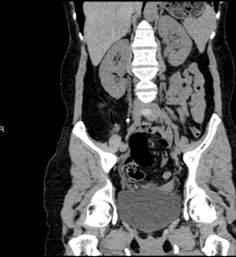

王春阳教授详细了解刘女士的病史,患者左侧输尿管全程扩张,左肾功能轻度受损,右肾积水,右肾功能未见异常,输尿管与膀胱连续性中断并且盆腔有液性暗区。

图一 术前泌尿系三维CT图二 术后3天泌尿系三维CT